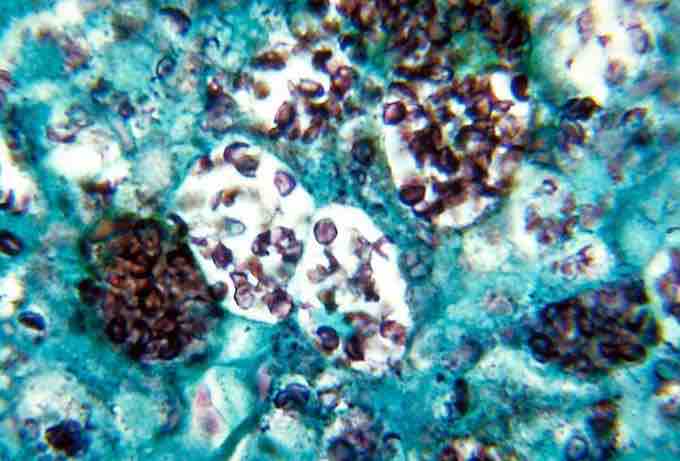

This is a Methenamine silver strain of Histoplasma capsulatum that shows histopathologic changes in the histoplasmosis.